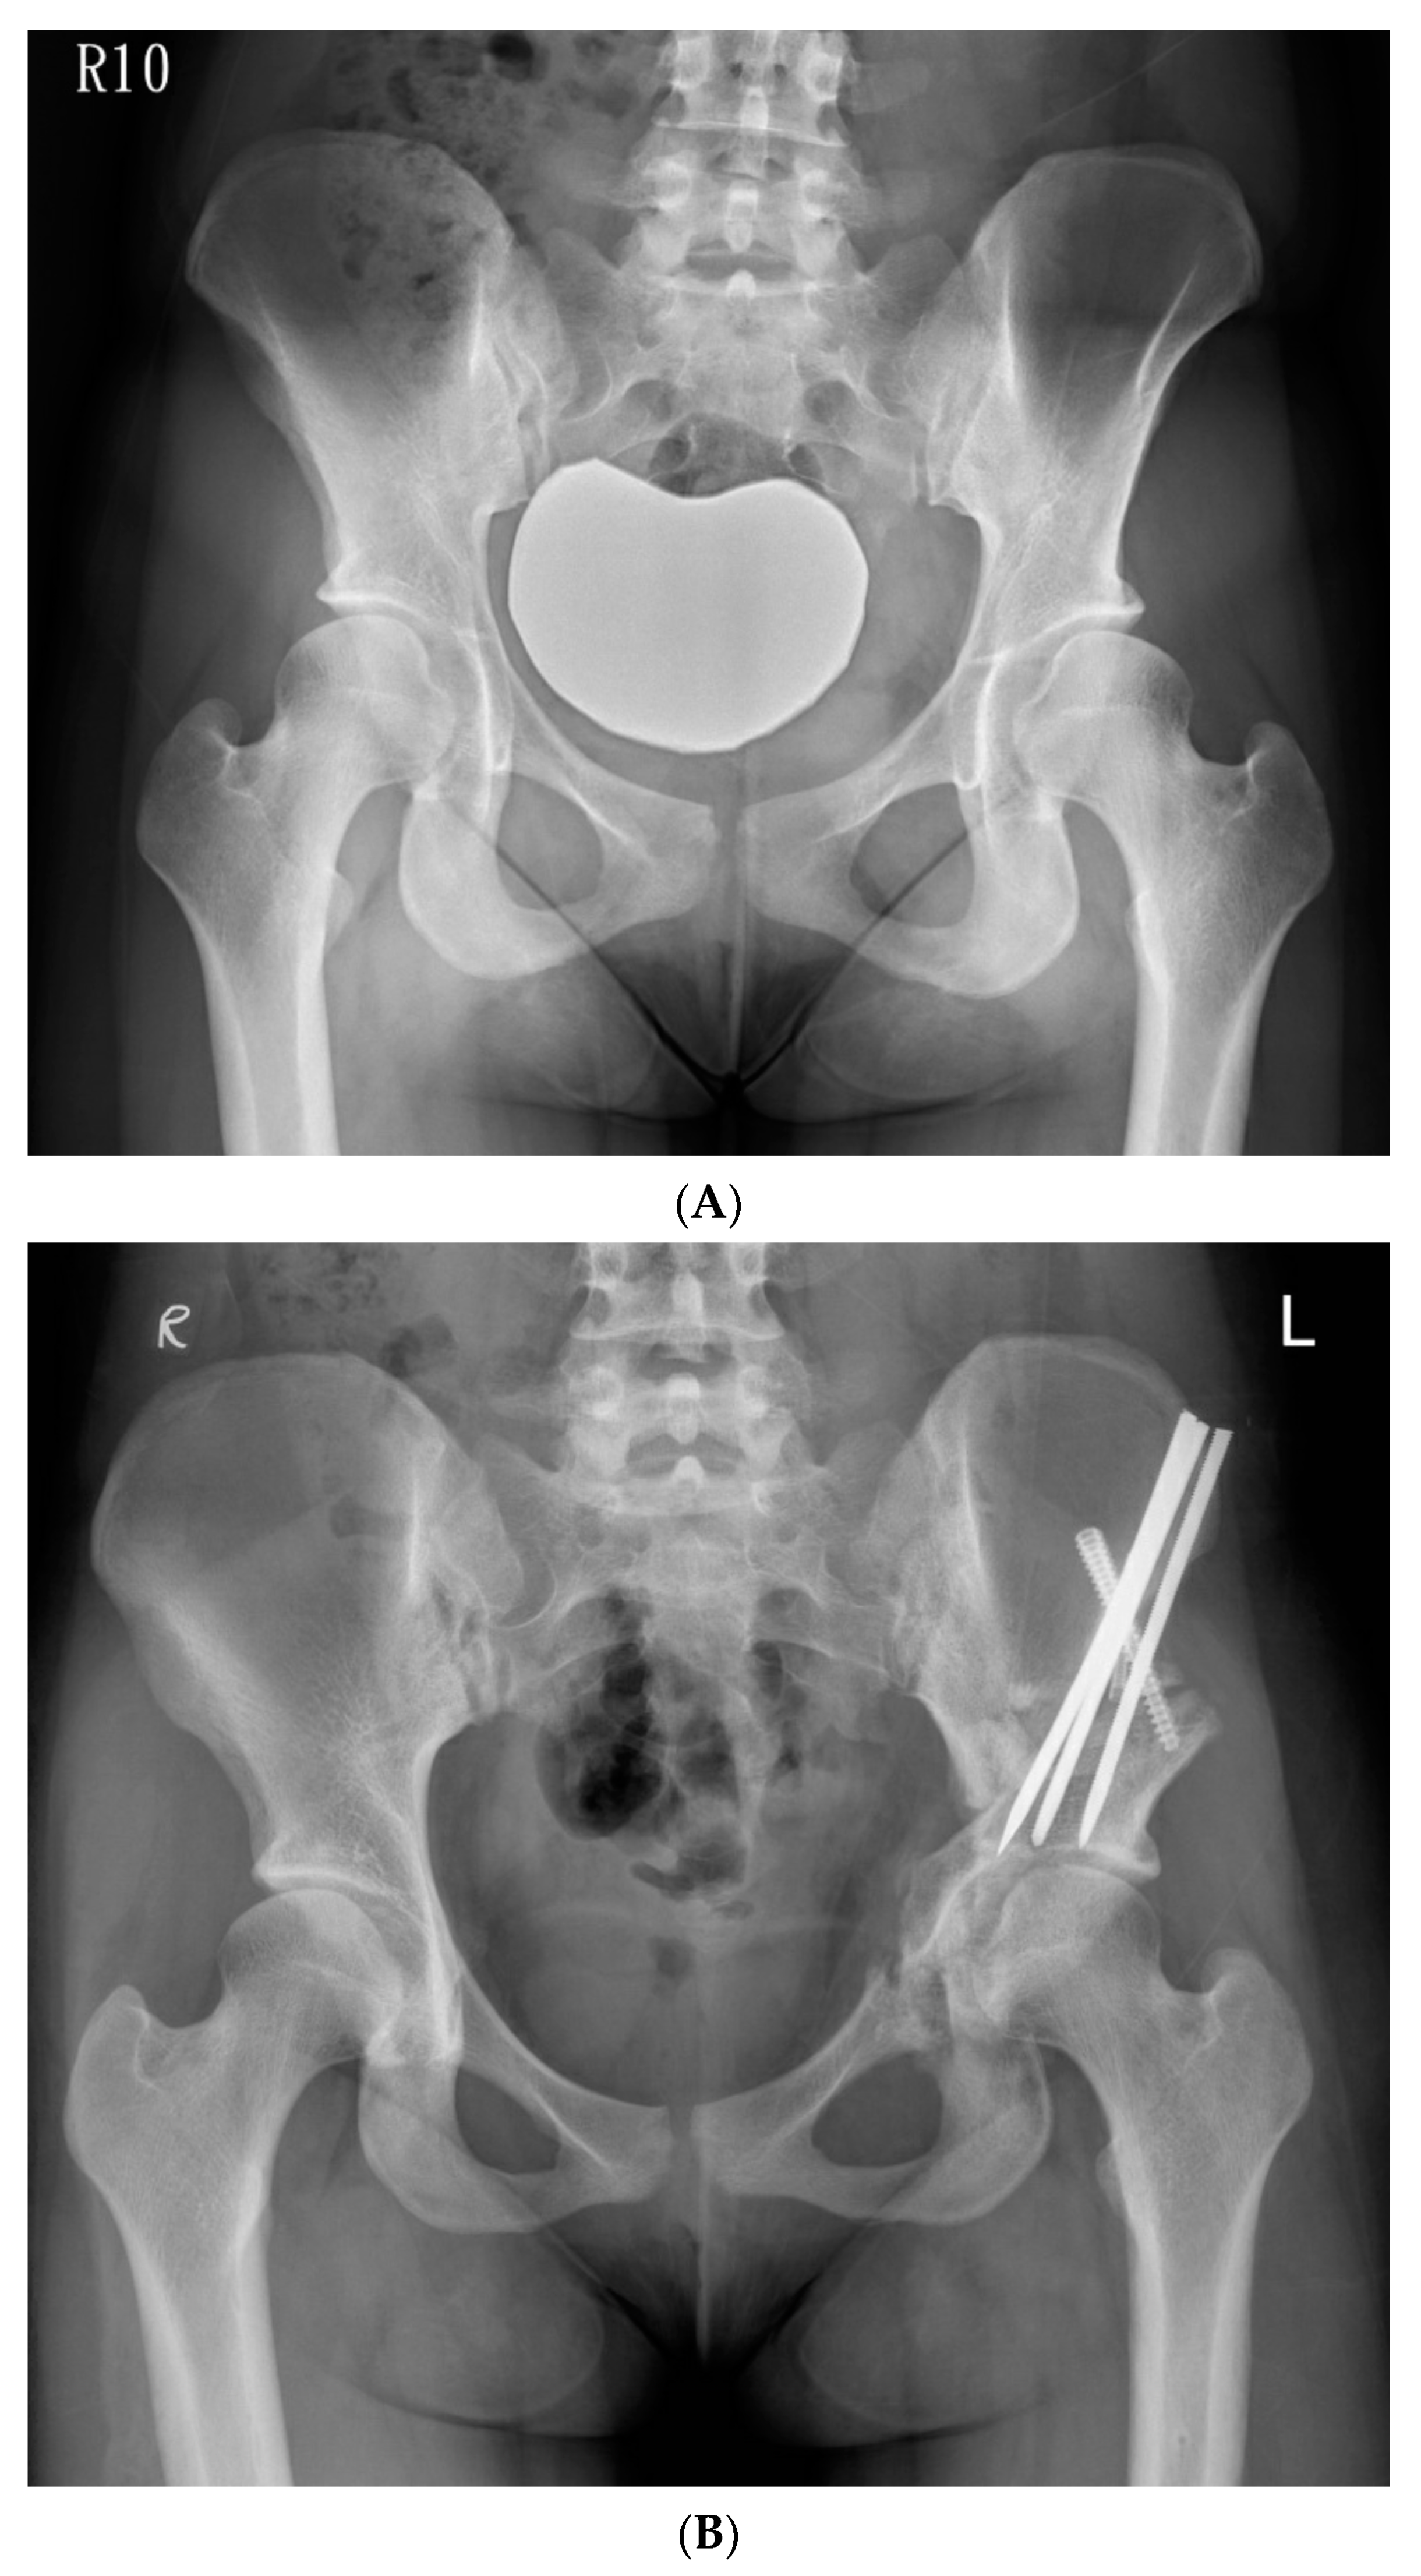

The hip was flexed and adducted to relax the medial soft tissues, and the osteotomy was made through the medial cortex. The osteotomy was extended from the posterior end of the iliac saw-cut and passed over the iliopectineal line, through the medial quadrilateral plate, and parallel to the anterior edge of the sciatic notch as observed through iliac oblique fluoroscopy, and was subsequently directed towards the ischial spine. We used a 30° angled, long-handled chisel to connect the anterior and posterior ischial cuts to complete the osteotomy of the posteroinferomedial corner of the quadrilateral plate. We used a bone clamp as a joystick to manipulate the periacetabular bone by lifting the acetabular fragment slightly towards the ceiling, creating an initial displacement, followed by a three-step movement of lateral, distal, and internal rotation. We inserted the artificial bone graft substitutes into the osteotomy site with multiple 6.0-mm cannulated screws and fixed the ASIS with a 4.5-mm cannulated screw augmented with a transosseous suture. A 1/8” hemovac drain was inserted, and the wound was then closed by layers. (Figure 3A,B).

Figure 3.

(A) Preoperative anteroposterior standing radiograph of a 19-year-old woman who underwent Ganz Osteotomy for symptomatic left hip dysplasia. (B) Postoperative anteroposterior standing radiograph showed good coverage of the femoral head.